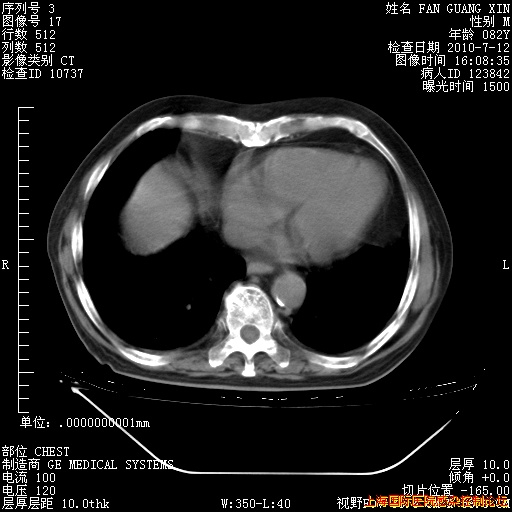

今天复查CT

今天CT

整整相隔30天的肺部CT好像有所好转啊。甲强龙减量第3天,需要观察体温。

海管,自昨日你和我通完话后,不知您岳父消化道症状有无缓解?体温怎样?阅读7.12日胸部ct,个人认为目前激素治疗是有效的,甲强龙减量是适宜的。因在抗痨治疗,需密切观察肝功、肾功能和血常规。不过,老年、长期住院和大量使用激素,很担心菌群失调发生